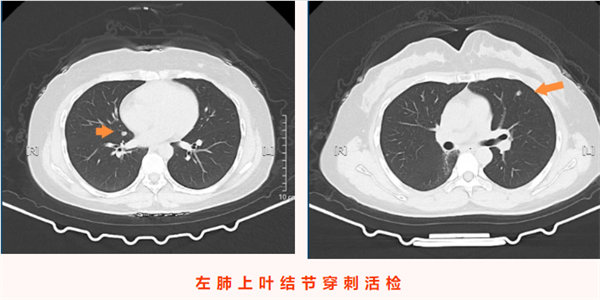

入院后,醫療團隊結合患者既往腺樣囊性癌病史、影像學檢查結果,術前綜合評估后高度懷疑雙側肺結節為腫瘤轉移灶。考慮到患者無明顯癥狀、病灶相對局限,為最大限度減少患者創傷、避免二次手術,團隊決定為其同期實施雙側肺結節診療手術——即CT引導下經皮左肺上葉微小結節穿刺活檢+微波消融術,同期對右肺結節行微波消融術。手術由科主任陳瑜主刀,副主任吳明君擔任助手,魏寶、張寶軍為第二助手。手術過程中,醫師團隊首先聚焦左肺上葉僅0.8cm×0.5cm的微小實性結節,在左側腋下及前外側胸壁精準標記,在患者平靜呼吸狀態下通過CT反復掃描確認穿刺參數,成功獲取活檢組織。并按計劃對左肺穿刺后的結節及右肺斜裂結節同期實施微波消融術,精準破壞雙側病灶組織。整個手術過程一氣呵成,同期完成雙側病灶診療,術中患者生命體征始終平穩。

術后,患者安返病房,生命體征穩定,無胸痛、咯血、氣胸等不適癥狀,飲食睡眠恢復良好。術后病理結果回報,明確左肺上葉結節為腺樣囊性癌轉移灶,與術前評估判斷一致,為后續診療方案制定提供了金標準依據。本例患者無任何癥狀,正是通過定期復查實現轉移病灶的早期發現;同時彰顯了“診斷+治療”一體化微創技術的臨床價值,為惡性腫瘤轉移灶的早期干預提供了高效、精準的診療范式,有力保障了腫瘤患者的長期生存質量。